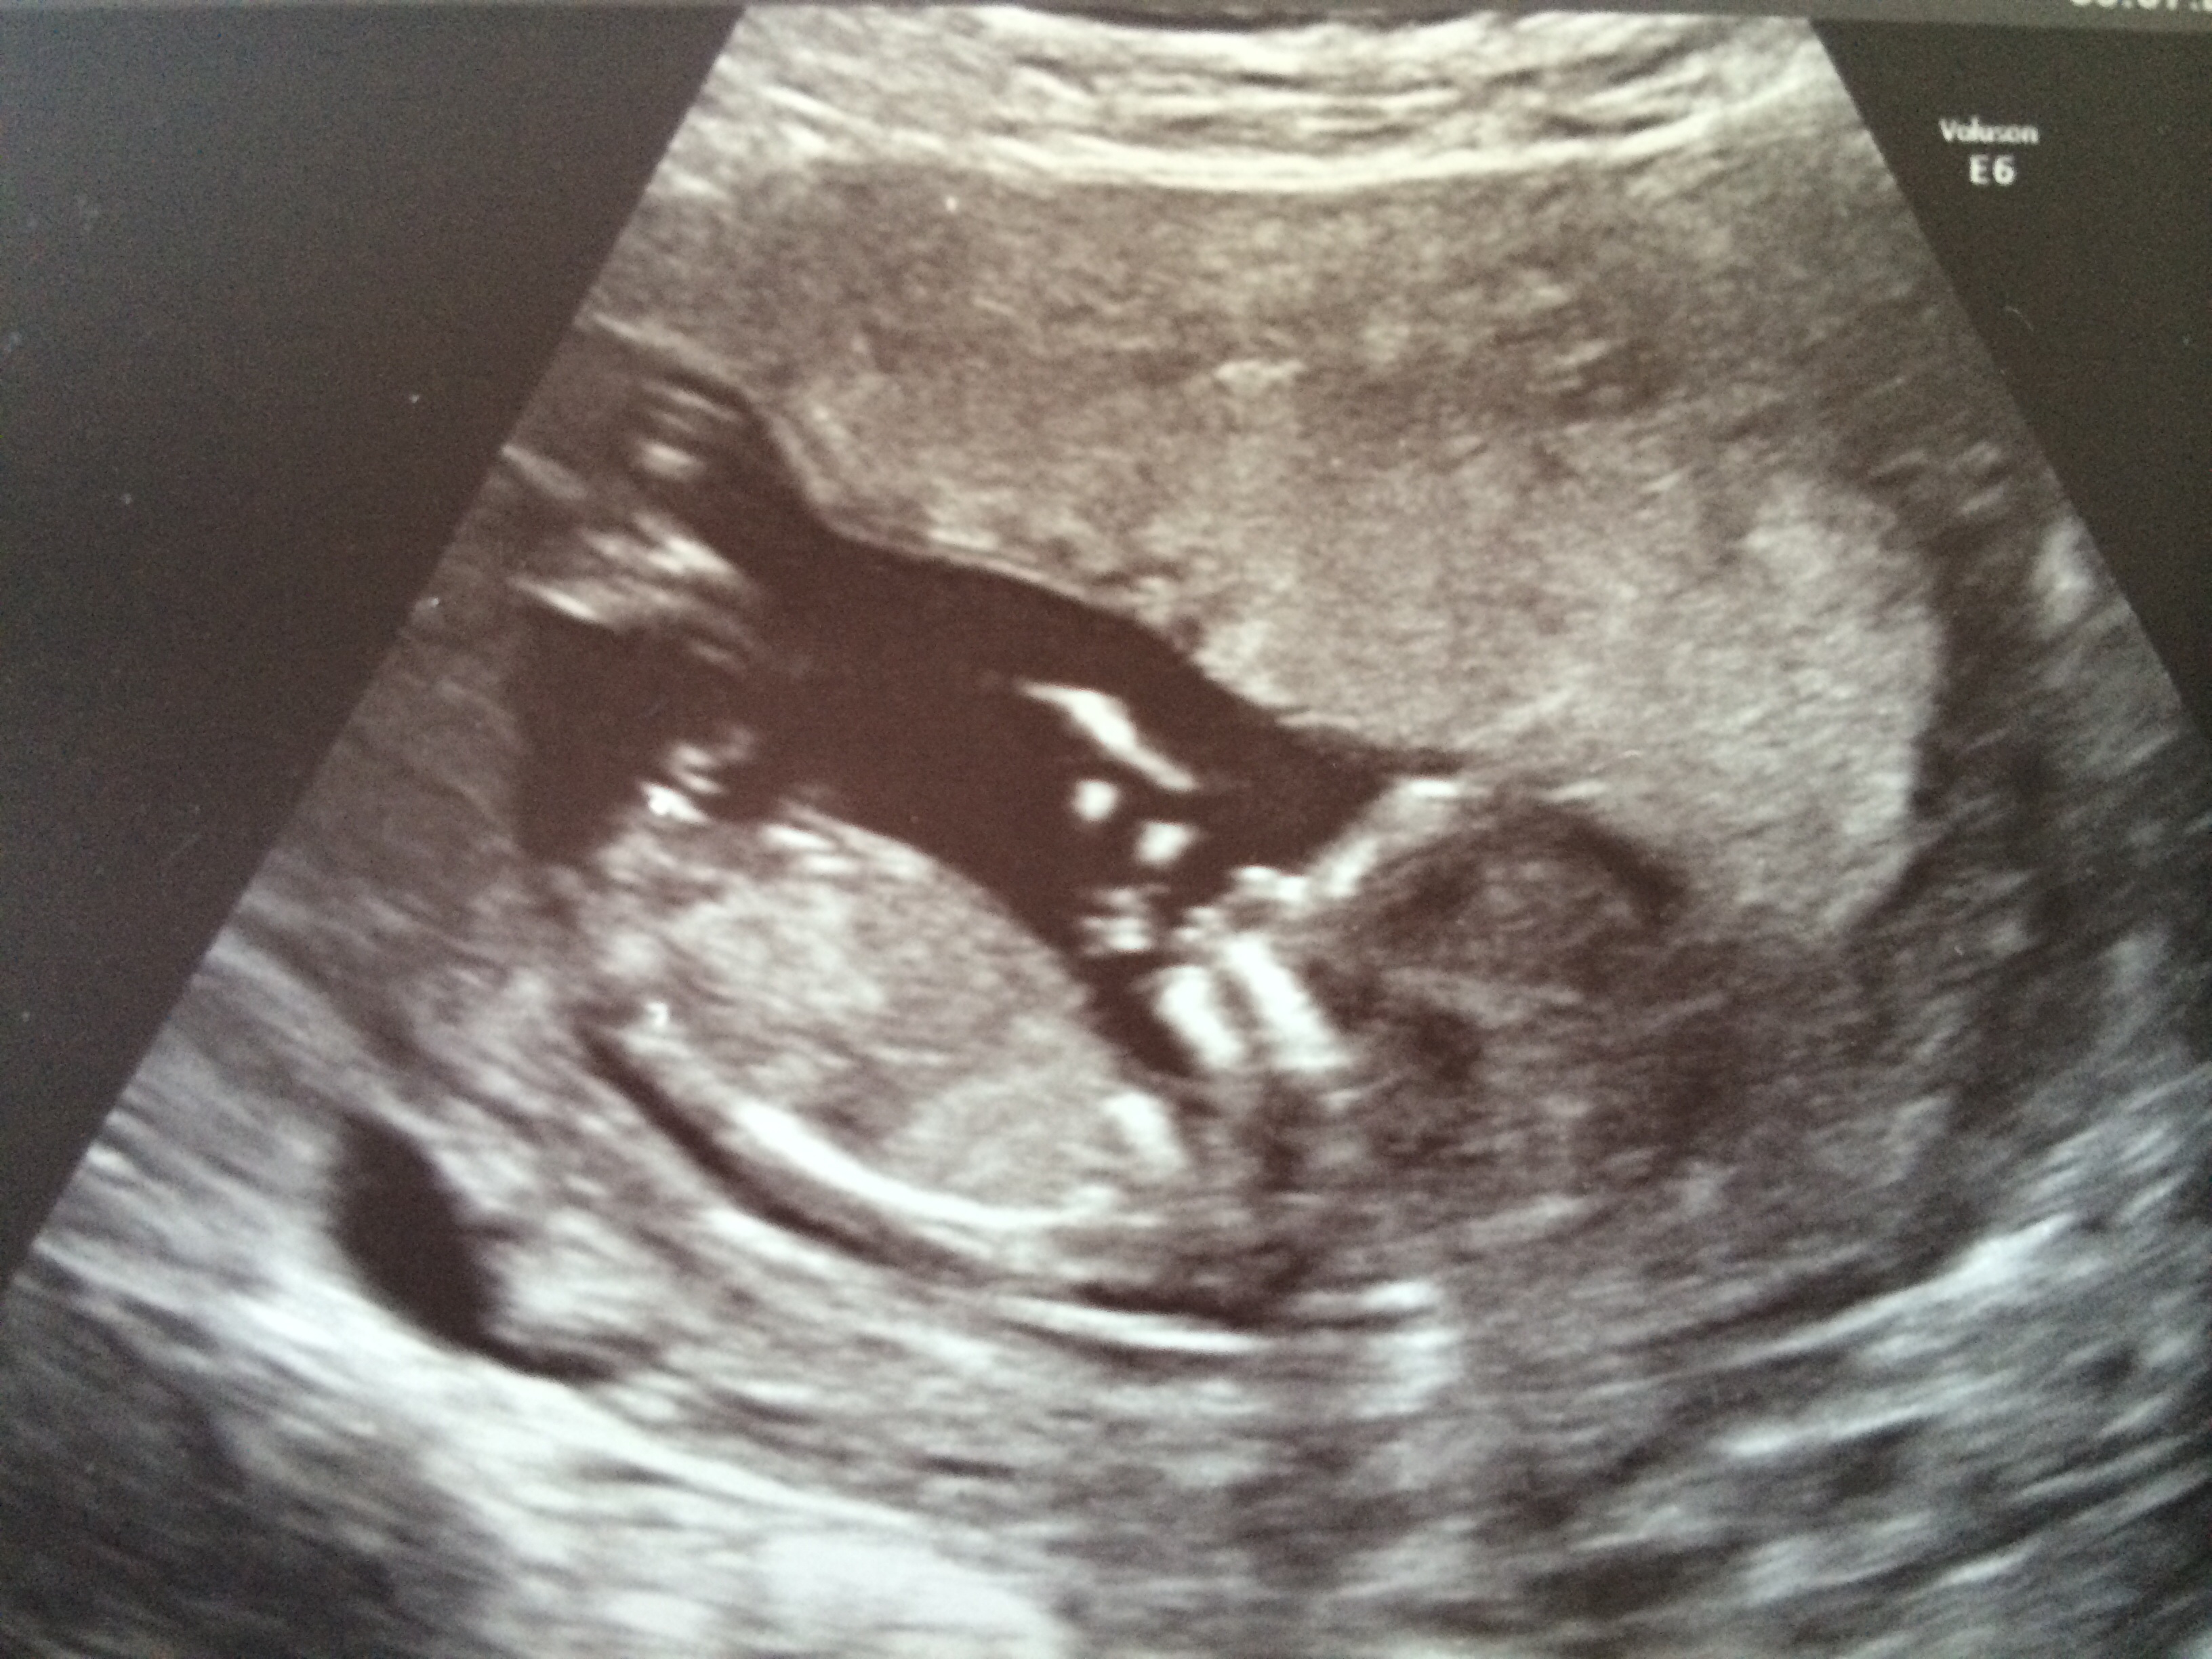

So, here are my 12w+4 pics:

Girl

A bit early, but lookin' girly!

I think there's a lot going on. Possibly boy.

I'm hesitant because although there is a straight line, there is also a bump on top thT could mean boy...hmmm I'll go with slight girl lean.

lean girl

maybe pink